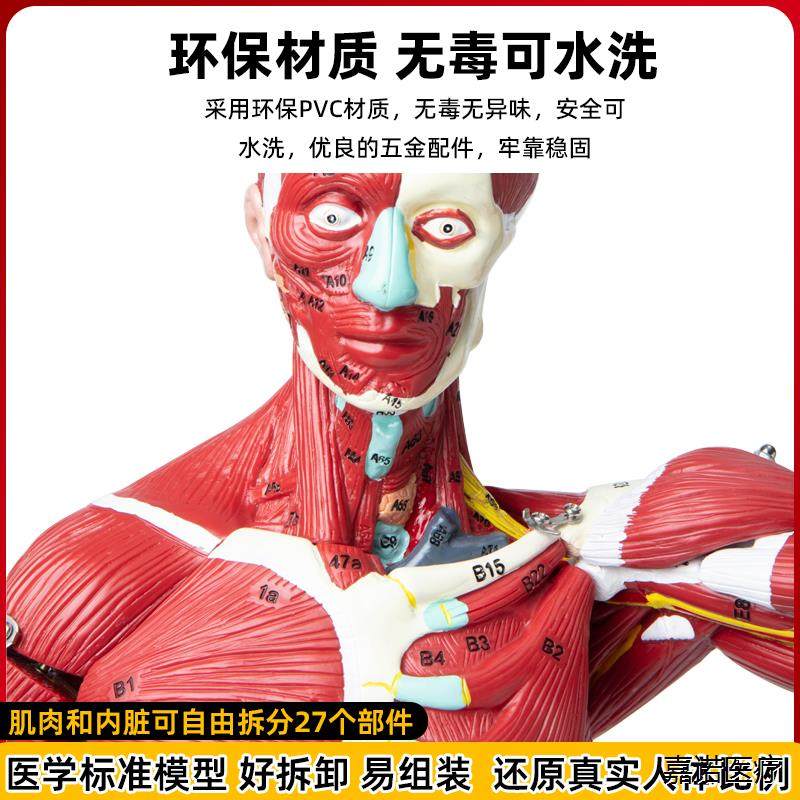

Human Body Muscle Internal Organ Disassembly Anatomy Structure Model Tissue Exercise Artificial Medical Teaching Aids

- Brand: Jianuo Medical

| Color Classification | 85 Human Muscle Internal Organs Removable Organ,50cm Muscle Model |